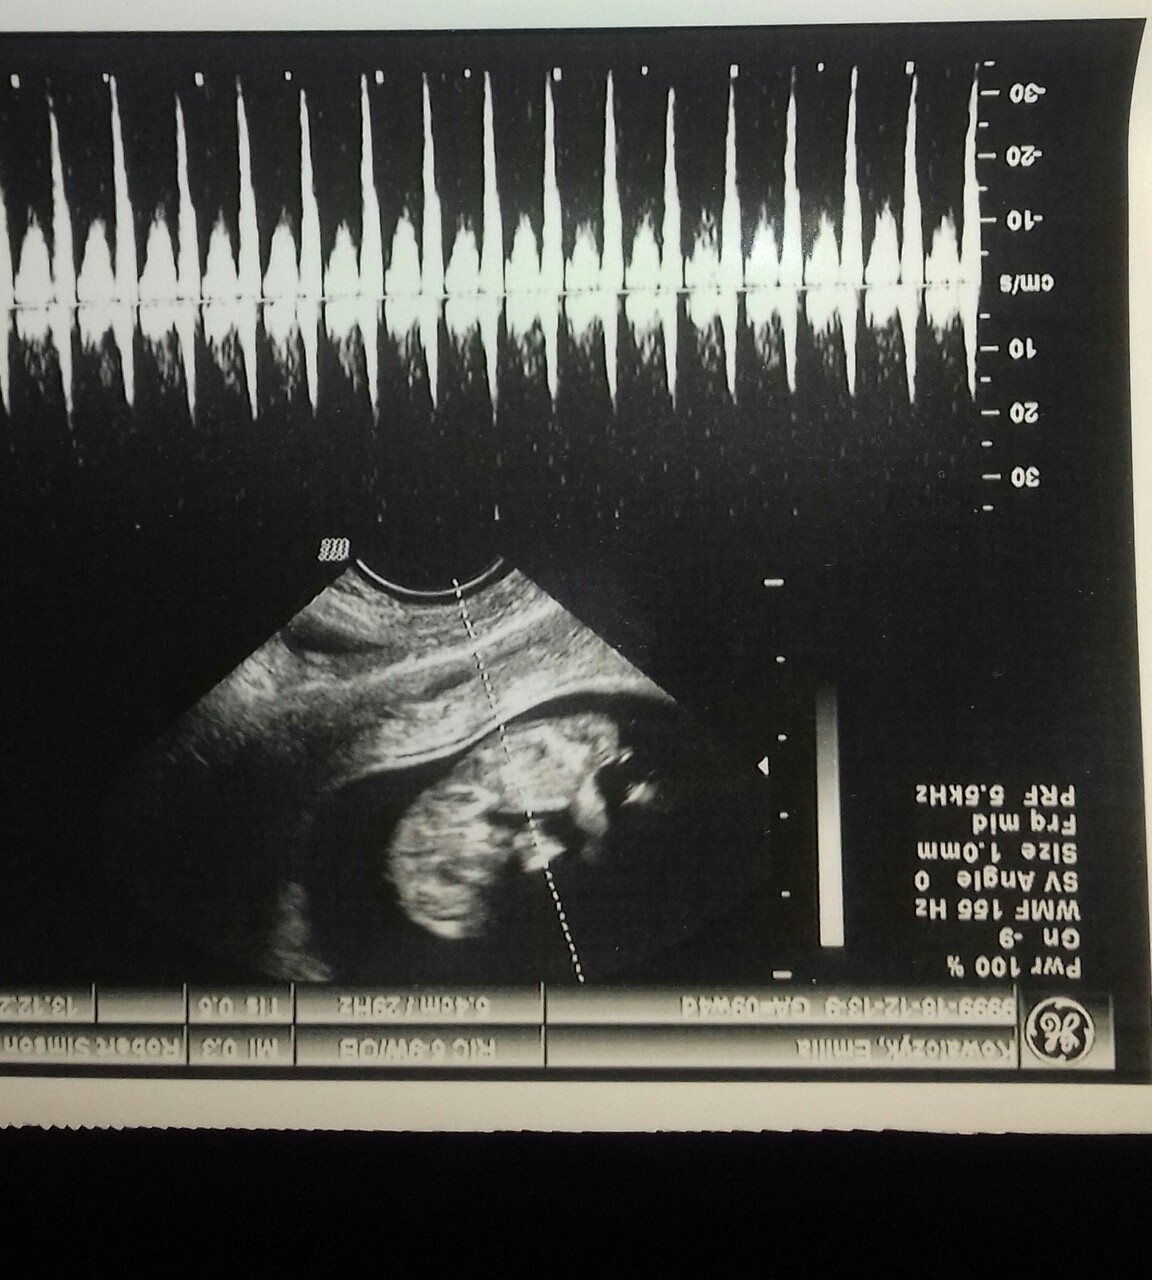

nie wiem gdzie ten wyrostek widac...bo moim zdaniem tam nic nie widac dziecko lezy w trudnej pozycji w klebek na serio nic tam nie widac...

A to ze dobry sprzet nic nie znaczy jak dziecko sie tak ulozylo;-) gdybys miala potty shoot ewentualnie dziecko z profilu jak mierzone jest crl to wtedy mozna by cos dojrzec a tak nic..a zgadywac bezsensu bo zawsze jest 50%;p